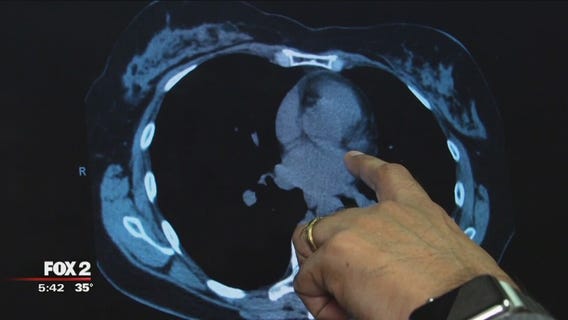

Scoring your calcium levels can give you life-changing news

A simple heart scan is available, for less than $100, that can predict your risk of a heart attack. The scan only takes about 15 minutes, too, and the results are life changing.

The Doctor Is In: Coronary Calcium Scan

A Cardiologist from Henry Ford Hospital answers questions from Fox 2 viewers.

A look at how coronary calcium scans can help determine your risk for heart disease.